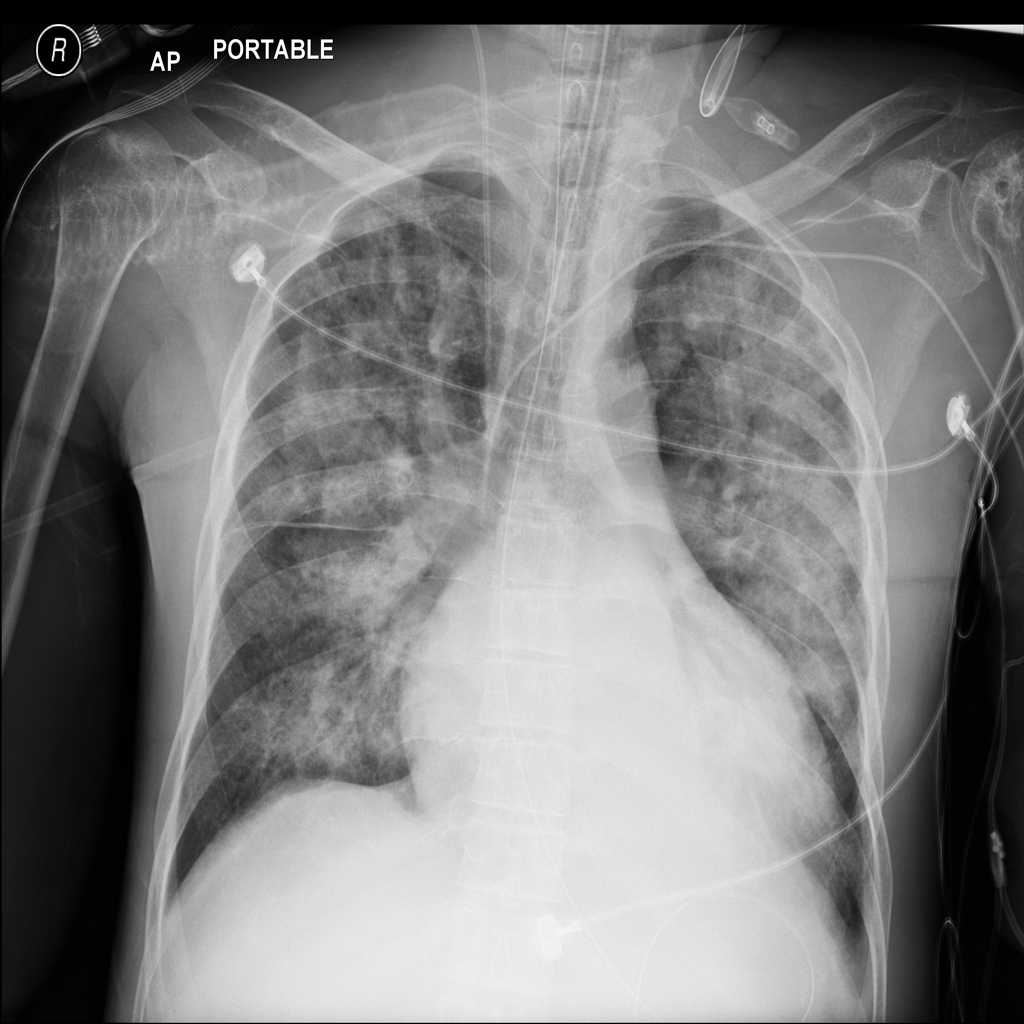

PAT-E828 · IMG-005Edema

PAT-E828 · IMG-005

AP